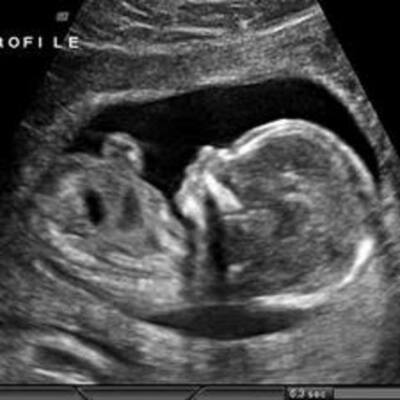

Pregnancy and Prenatal Development